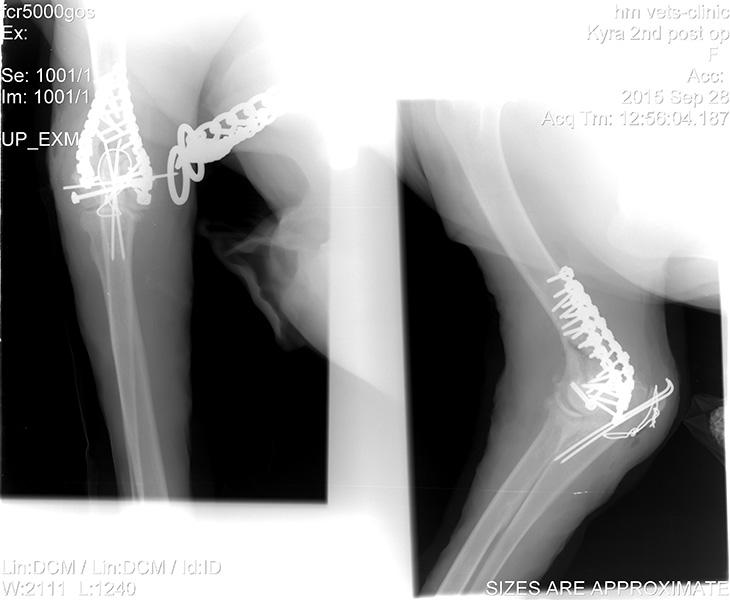

Ορθοπεδική

Ορθοπεδική

Το κτηνιατρείο hm vets αναλαμβάνει ψηφιακή ακτινογραφία, έλεγχο δυσπλασίας ισχίου, ορθοπεδική-νευροχειρουργική, χειρουργική μαλακών μορίων, οφθαλμολογία, εσωτερική παθολογία και εργαστηριακές εξετάσεις (αίματος, βιοχημικές, ανοσολογικές, ορμονολογικες, μοριακές και ιστοπαθολογικές).

Το κτηνιατρείο hm vets αναλαμβάνει ψηφιακή ακτινογραφία, έλεγχο δυσπλασίας ισχίου, ορθοπεδική-νευροχειρουργική, χειρουργική μαλακών μορίων, οφθαλμολογία, εσωτερική παθολογία και εργαστηριακές εξετάσεις (αίματος, βιοχημικές, ανοσολογικές, ορμονολογικες, μοριακές και ιστοπαθολογικές).